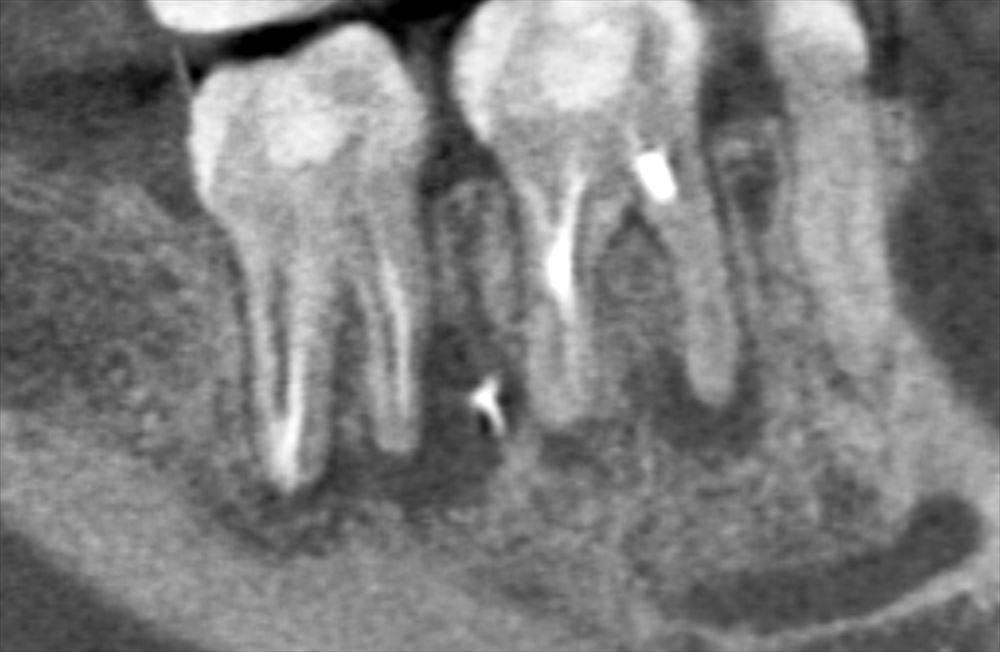

右下6.7に根尖性歯周炎。7番の近心は大きな透過像。6番の近心根は狭窄している。。。。難症例です。

通法通り精密根管治療

レーザー

根管治療の基本をきちっと守る。

厳密に根管充填